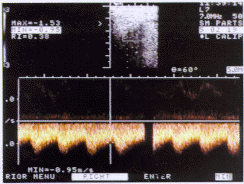

图2 血流最大流速MAX=1.53m/s,阻力指数为0.38